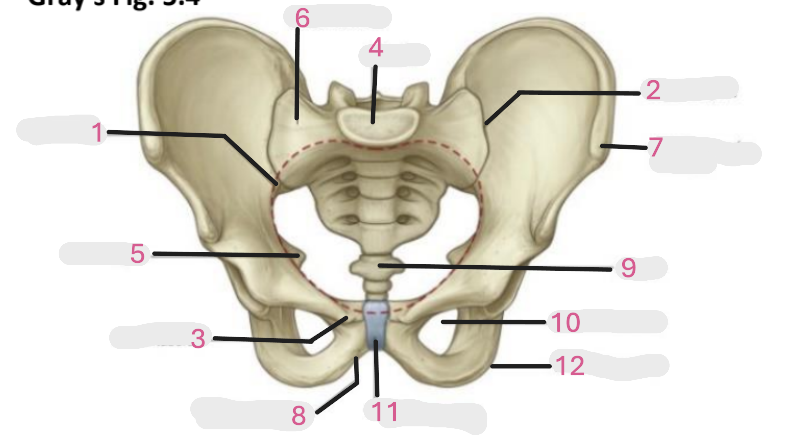

Where is the pelvic inlet

1

Where is the sacro-iliac joint

2

Where is the pubic tubercle

3

Where are the S1 body

4

Where is the ischial spine

5

Where is the ala of sacrum

6

Where is the anterior superior iliac spine

7

Where is the ischiopubic ramus

8

Where is the coccyx

9

Where is the obturator foramen

10

Where is the pubic symphysis

11

Where is the ischial tuberosity

12